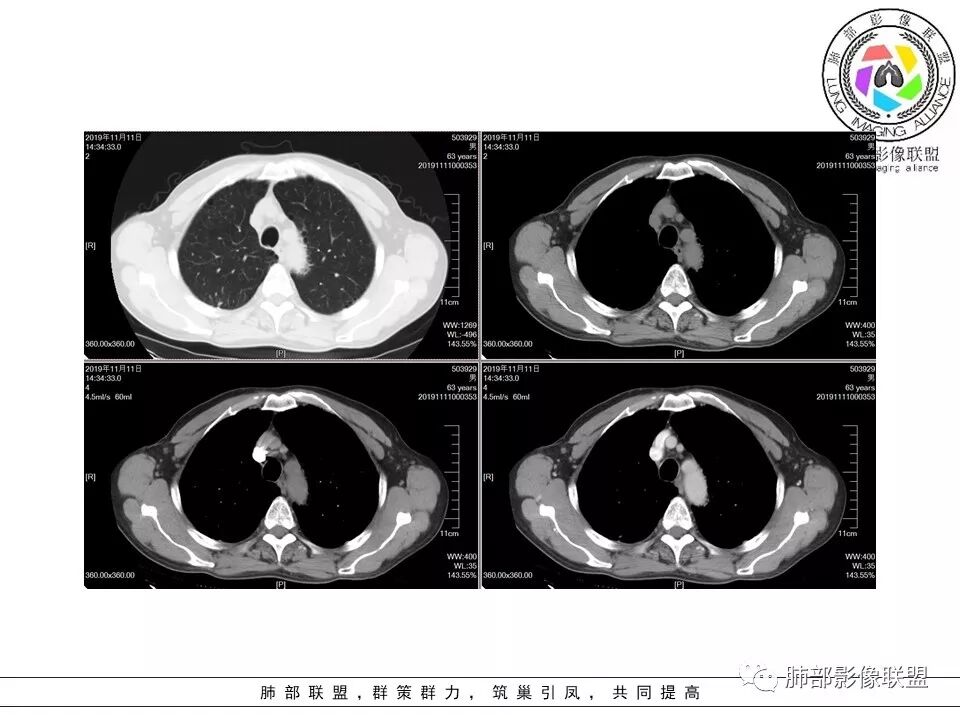

晕晕菜:患者中老年男性,体检发现肺部占位。既往既往有类风湿关节炎,长期口服激素胸CT:间隔旁肺气肿,右肺上叶后段胸膜下病变,与胸膜宽基底相连,局部胸膜明显增厚,病灶内可见空洞,病灶周围有散在卫星灶。左肺下叶背段胸膜下实变,病灶边界清楚,与长轴与胸膜平行,病灶周围可见软毛刺,纵隔窗可见病灶与胸膜呈糊墙征。 总体考虑良性病变。右上:结核?左下:隐球菌?

小赵:老年男性,类风湿及长期服药史。胸部CT所见右肺上叶及左肺下叶胸膜下多发病灶,右肺上叶病灶内见空洞及液平面,内壁光滑,周围散在条索及小结节样卫星灶,邻近胸膜增厚,增强扫描病灶轻度强化。左肺下叶病灶长轴平行于胸膜,周围见边界不清磨玻璃密度影,与邻近胸膜成糊墙改变。增强扫描病变成不均匀明显强化,内见强化血管影。诊断一元考虑双肺炎性病变,隐球菌可能。二元考虑右肺上叶结核,左肺下叶隐球菌感染,粘液腺癌待排。

破风5:胸部CT:右上叶胸膜下病变,与胸膜宽基底相连,累及胸膜,病灶内可见空洞,洞壁光滑,病灶周围有散在卫星灶。有类风湿激素口服历史,结核首先考虑。左肺下叶背段胸膜下实变,病灶边界清楚,与长轴与胸膜平行,血管伸入,纵隔窗可见糊墙征。考虑良性病变,隐球?总体,右上肺结核,左下肺隐球,CTD-ILD

流心明智:患者,老年男性,既往有类风湿关节炎,长期口服激素史。胸CT:间隔旁肺气肿,右肺上叶后段胸膜下病变,与胸膜宽基底相连,局部胸膜增厚,病灶内向肺门侧空洞,病灶周围卫星灶。考虑炎性病灶。左肺下叶胸膜下气肿背景边缘实变、边界清楚、有膨隆、滋养血管征,软毛刺、多结节融合、糊墙征。 总体考虑:良性病变,右上:结核?左下:隐球菌?左下鉴别Ca。

南边:糊墙,长轴与胸膜平行;边缘收缩+膨隆;脐凹征

常规:隐球菌与癌鉴别

脐凹征,高度提示恶性

因为其与胸膜的关系与右上叶的不一致,所以不能一元论

而且周围的表现不一致

还有就是间质性病变基础上,恶性变的几率很高